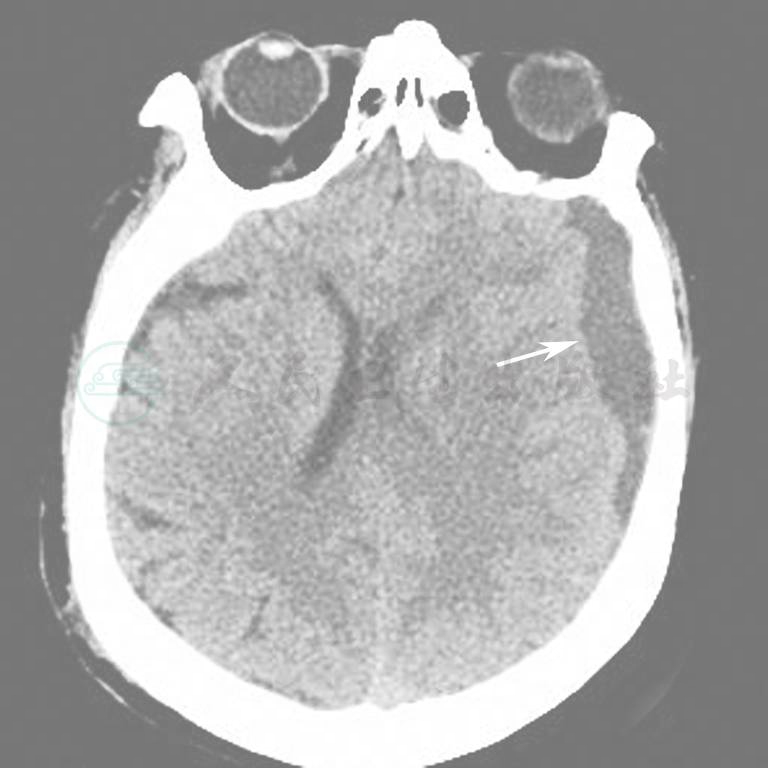

图9  脑干右份出血

图10  颅内出血(硬膜外)

图11  双侧颅内出血(硬膜下)